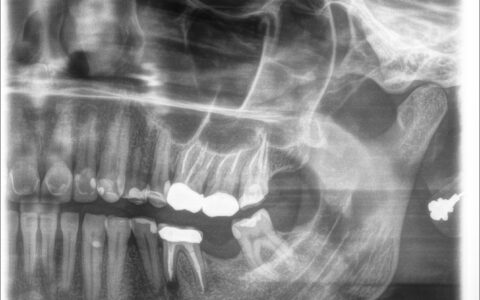

Zdjęcie RTG pacjentki przed implantacją oraz po wszczepieniu 2 implantów.